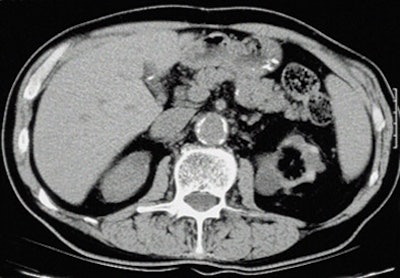

| Above: Small kidneys with cysts. Below: Typical ESRD pattern of small, smooth kidneys. Typical symtoms include edema, low urine output, confusion, weakness, flank pain, or nausea and vomiting. |